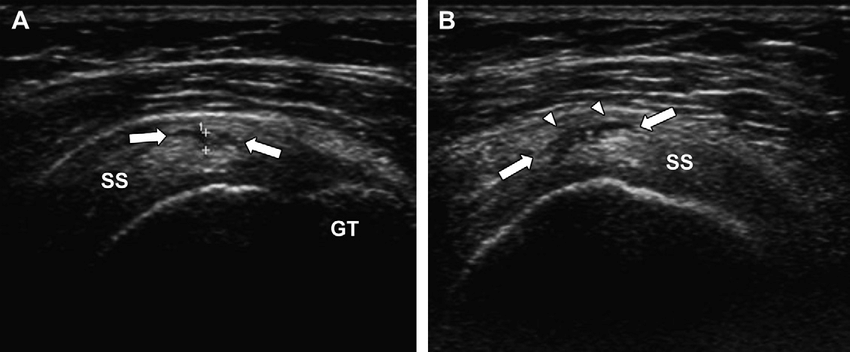

Rotura parcial articular (cara profunda): es la más frecuente. Se produce en la interfase articular del tendón, la que está en contacto con la cabeza humeral.

Rotura parcial bursal (cara superficial): afecta a la cara que contacta con la bursa subacromial-subdeltoidea. Son menos frecuentes y a veces asociadas a impingement mecánico externo.

En roturas de la cara articular, el defecto se sitúa en la interfase profunda del tendón. En las de la cara bursal, en la interfase superficial, lo que puede acompañarse de engrosamiento de la bursa o líquido

El signo principal de una rotura parcial es un defecto focal hipoecoico en el espesor del tendón. A diferencia de la anisotropía, este defecto:

- Persiste al corregir el ángulo de incidencia.

- Tiene márgenes definidos y cierta morfología reproducible (normalmente fusiforme o triangular).

- Se localiza de forma consistente en los dos planos de exploración (longitudinal y transversal).